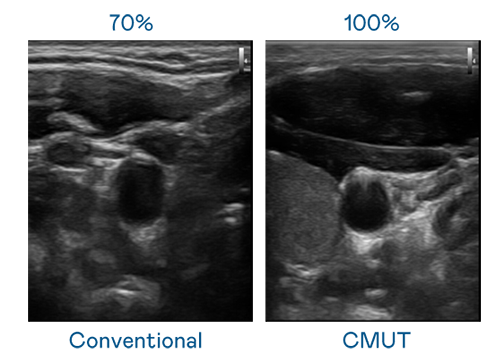

CMUT 技术是一种用电容式微机电元件来产生超音波讯号的技术。与传统 PZT 压电式技术相比,CMUT 频宽增加 30%,更宽频的超音波讯号让影像解析度大幅提升,是实现高影像品质医疗超音波扫描、促进精准医疗发展的关键技术。

大频宽带来超清晰影像

超音波影像的解析度高低,首先取决于探头能发出的讯号频宽。优发国际 CMUT 可提供高清晰的超音波讯号,提供高频宽、高灵敏度、影像纹理细节更高的超音波影像,协助医护人员缩短影像判读时间及利用精准的医疗影像进行诊断。